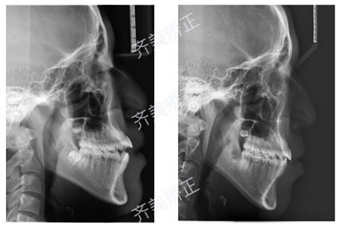

牙齿问题:牙齿错合

治疗周期:1年半多

这就是开合!